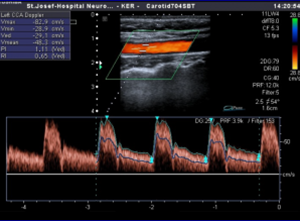

Εικόνα 1: Απεικόνιση του εξωκράνιου και ενδοκράνιου τμήματος της έσω καρωτίδας αρτηρίας

Κατά συνέπεια, εγκεφαλικά αγγεία καλούνται όλες εκείνες οι αρτηρίες και φλέβες που συμμετέχουν στην αιματική κυκλοφορία του εγκεφάλου. Από ανατομικής άποψης τα εγκεφαλικά αγγεία χωρίζονται στο εξωκράνιο τμήμα τους, που βρίσκεται εκτός της κεφαλής, και στο ενδοκράνιο τμήμα τους, το οποίο εντοπίζεται εντός της κρανιακής κοιλότητας (Εικόνα 1).